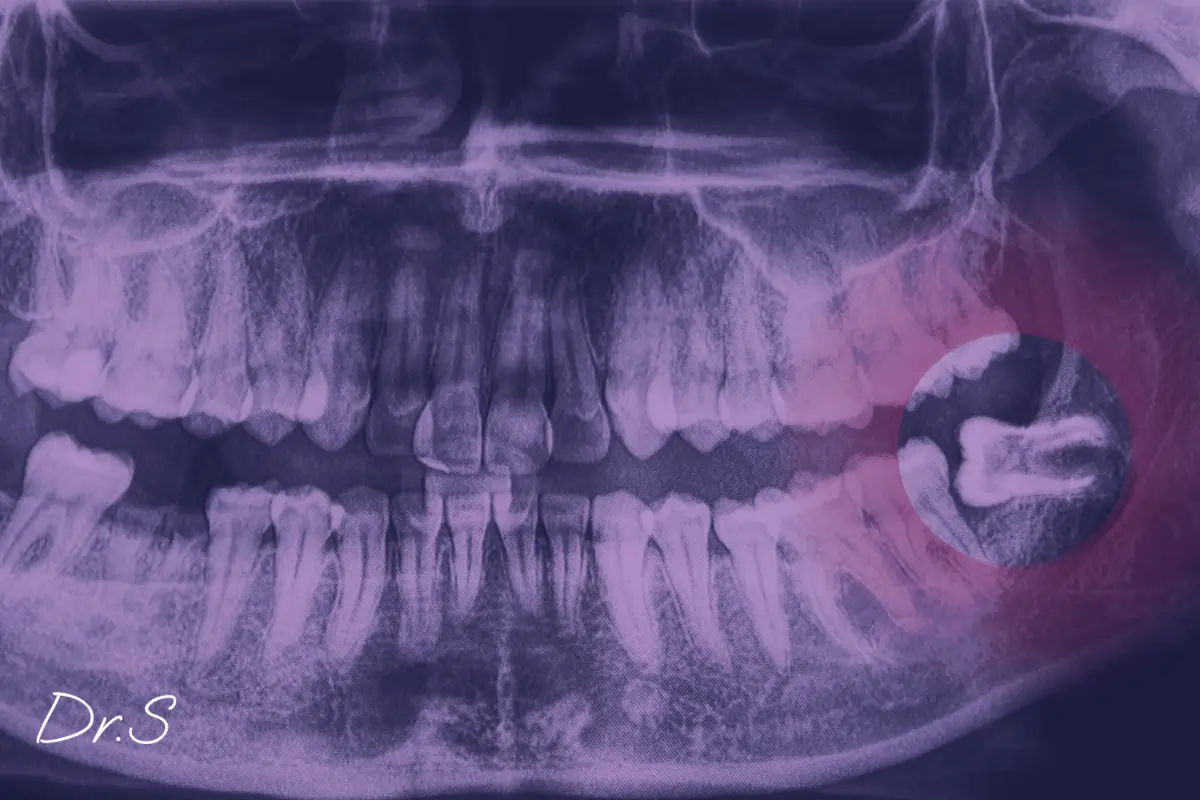

Lorsque la dent pousse de travers ou exerce une pression latérale, elle perturbe l’alignement naturel de la mâchoire. Une imagerie dentaire, souvent panoramique ou en 3D, permet alors d’orienter le diagnostic.

L’extraction est indiquée lorsqu’il y a répétition des épisodes douloureux, infection chronique, ou risque sur les dents adjacentes. Certains patients, même sans gêne, présentent des dents de sagesse incluses pouvant créer des kystes à long terme.

Dans ces cas, je propose une discussion individuelle, avec une évaluation morphologique de chaque dent à l’aide d’une imagerie. L’intervention est alors planifiée en dehors des phases inflammatoires, dans des conditions de sécurité optimales.

Le suivi à partir de 16-17 ans permet d’observer l’éruption ou la position des dents de sagesse par des radiographies panoramiques. C’est souvent à cet âge que je propose un premier bilan, même en l’absence de symptômes.